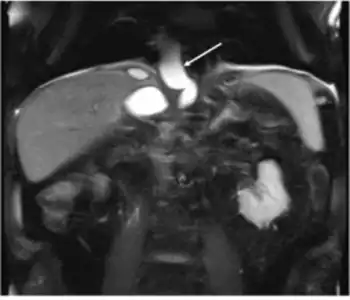

Pseudocyst extends through the hiatus opening to mediastinum

The most common and effective method of diagnosing a pancreatic pseudocyst is with a CT scan. A pseudocyst generally appears as a fluid-filled mass. In some instances, other methods must be used to distinguish between a normal cyst and a pseudocyst.[3] This is usually accomplished with endoscopic ultrasound or with fine needle aspiration.[2]